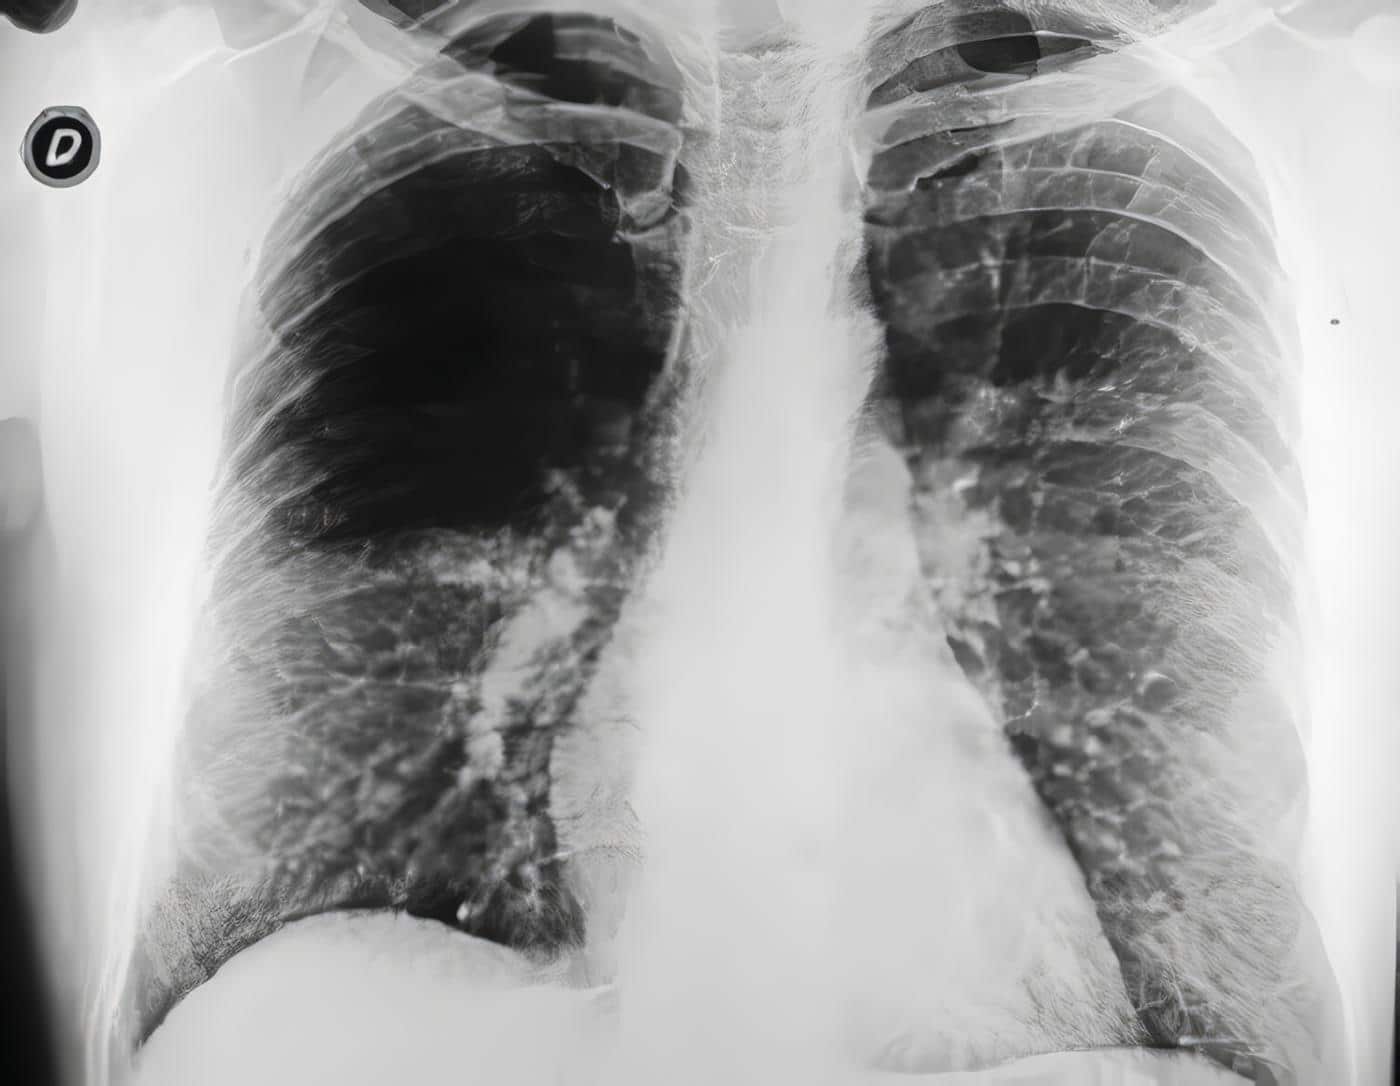

La radiografía de tórax fue anormal en todos los pacientes, presentando zonas de ocupación alveolar, cavitaciones, lesiones compatibles con bronquiectasias y una imagen sugestiva de micetoma. La TAC fue realizada en la mitad de los pacientes confirmando lesiones cavitarias, ocupación alveolar y bronquiectasias.

Figura 2. Paciente de sexo femenino, de 70 años, con hemoptisis masiva por bronquiectasias tuberculosas. (a) arteriografía bronquial derecha, con tortuosidad y dilatación de las ramas bronquiales,. con fístulas a las arterias pulmonares y transcolateralización, como signos de hemorragia. (b) Control post embolización con gelfoam + alcohol absoluto, con oclusión total y remisión de los síntomas.